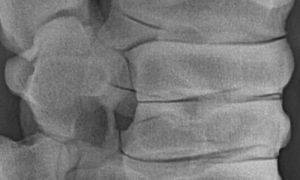

Digitales Röntgen

Röntgenaufnahme einer Pferdewirbelsäule

Zur Beurteilung des Skelettsystems.